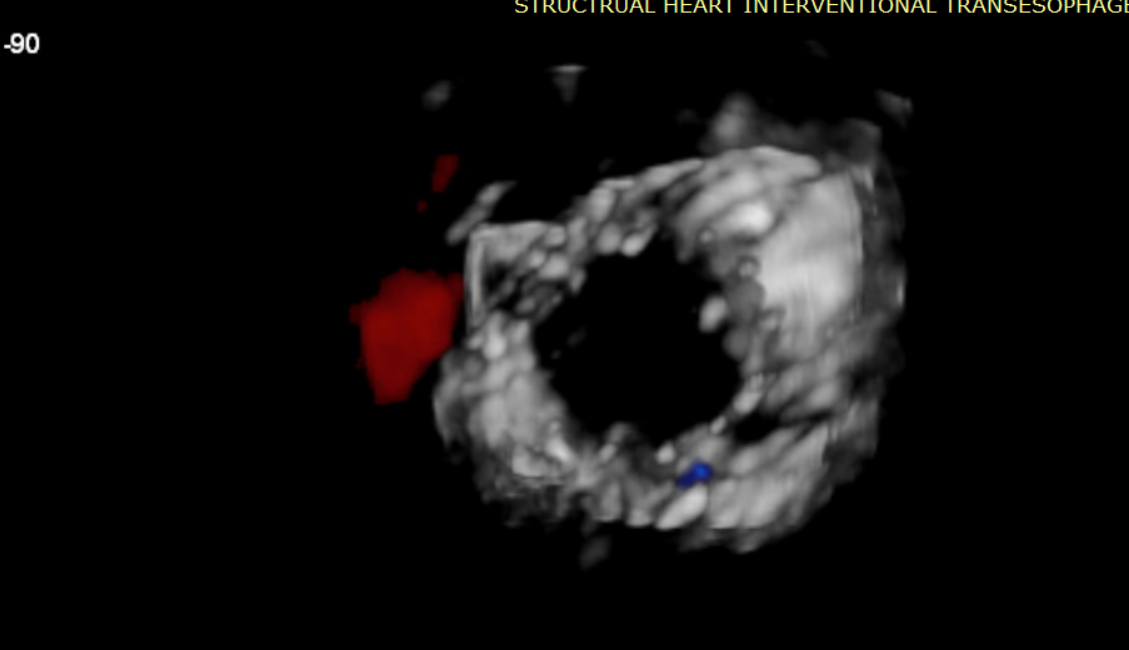

近日,美國紐約Montefiore醫學中心(Montrefiore Medical Center)的Azeem Latib教授團隊成功應用LuX-Valve Plus經血管三尖瓣置換系統為兩位三尖瓣大量反流的患者完成三尖瓣置換手術。術后超聲顯示人工三尖瓣植入穩定,瓣葉啟閉良好,僅殘余微量瓣周漏。患者于手術室即刻拔除氣管插管,血流動力學改善顯著。此次手術是LuX-Valve Plus于紐約的首次臨床應用,治療效果優異。

經過Azeem Latib教授帶領的多學科團隊討論,本次接受治療的兩位患者均為外科手術高危;且受限于影像和解剖結構的局限性,其他的經導管修復、置換系統均不適用。而LuX-Valve Plus獨特的錨定機制(即脫離徑向支撐力的“室間隔錨定”設計理念)和對術中超聲影像的低要求,使得Azeem Latib教授團隊認為這一中國創新醫療器械可以對這兩名患者進行有效治療。

術后Azeem Latib教授對LuX-Valve Plus經血管三尖瓣置換系統的器械性能和治療效果大為稱贊,并且認為LuX-Valve Plus的手術體驗非常好。從治療效果來看,術后即刻超聲顯示三尖瓣反流幾乎完全消失,血流動力學改善顯著,患者恢復快。在面對復雜解剖結構、超聲影像質量不佳、有起搏導線干擾時,Lux-Valve Plus也體現了極強的適應性。Thomas Modine教授參與了術中指導,他同樣再次肯定了LuX-Valve Plus術中操作的便捷性,認為LuX-Valve Plus容錯率高,對術中影像的依賴小,并表達了后期希望可以更多地應用LuX-Valve Plus三尖瓣置換系統于臨床實踐,讓更多的三尖瓣重度反流患者盡早獲益,改善預后。